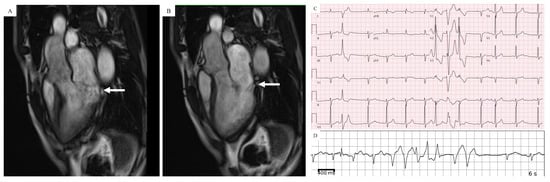

6. Cardiac Magnetic Resonance (CMR) Imaging

- Scatteia, A.; Pascale, C.E.; Gallo, P.; Pezzullo, S.; America, R.; Cappelletti, A.M.; Dalla Vecchia, L.A.; Guarini, P.; Dellegrottaglie, S. Abnormal Papillary Muscle Signal on Cine MRI as a Typical Feature of Mitral Valve Prolapse. Sci. Rep. 2020, 10, 9166. [Google Scholar] [CrossRef] [PubMed]

- Han, Y.; Peters, D.C.; Salton, J.C.; Bzymek, D.; Nezafat, R.; Goddu, B.; Kissinger, K.V.; Zimetbaum, P.J.; Manning, W.J.; Yeon, S.B. Cardiovascular magnetic resonance characterization of mitral valve prolapse. JACC Cardiovasc. Imaging 2008, 1, 294. [Google Scholar] [CrossRef]

- Lee, J.H.; Uhm, J.S.; Suh, Y.J.; Kim, M.; Kim, I.S.; Jin, M.N.; Cho, M.S.; Yu, H.T.; Kim, T.H.; Hong, Y.J.; et al. Usefulness of cardiac magnetic resonance images for prediction of sudden cardiac arrest in patients with mitral valve prolapse: A multicenter retrospective cohort study. BMC Cardiovasc. Disord. 2021, 21, 546. [Google Scholar] [CrossRef] [PubMed]